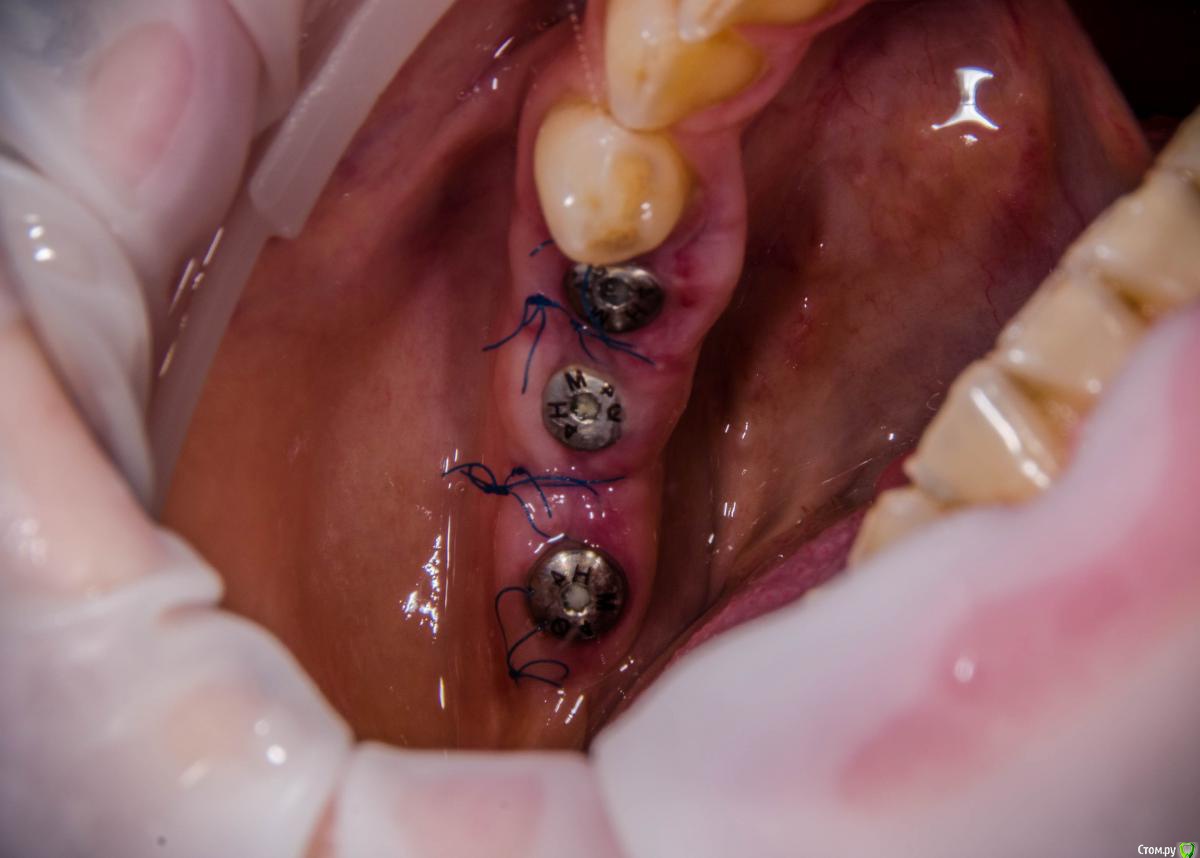

kamranchick Опубликовано 8 февраля, 2017 Автор Поделиться Опубликовано 8 февраля, 2017 А что и какой размер ставили?Послабляющий распил не делали?я тут не делал распилы, тут нет расщепления3,5-8,5 Ссылка на комментарий

kamranchick Опубликовано 8 февраля, 2017 Автор Поделиться Опубликовано 8 февраля, 2017 Спасибо за публикацию.Какова ширина гребня?5мм сверху в области кристального модуля имплантата дальше около 7мм) Ссылка на комментарий